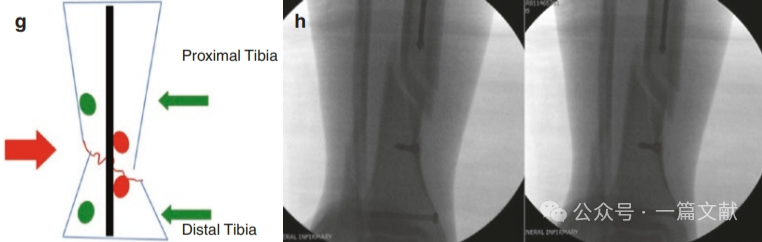

2,阻挡钉离中线和骨折线的距离目前尚无定论,一般推荐离骨折线约1-3cm,离中线越近越安全(6-7mm)。具体根据骨折形态和髓内钉直径而定,离骨折线太近易造成继发骨折,离中线太近则可能阻碍主钉置入,太远又可能无复位效果,如下图: